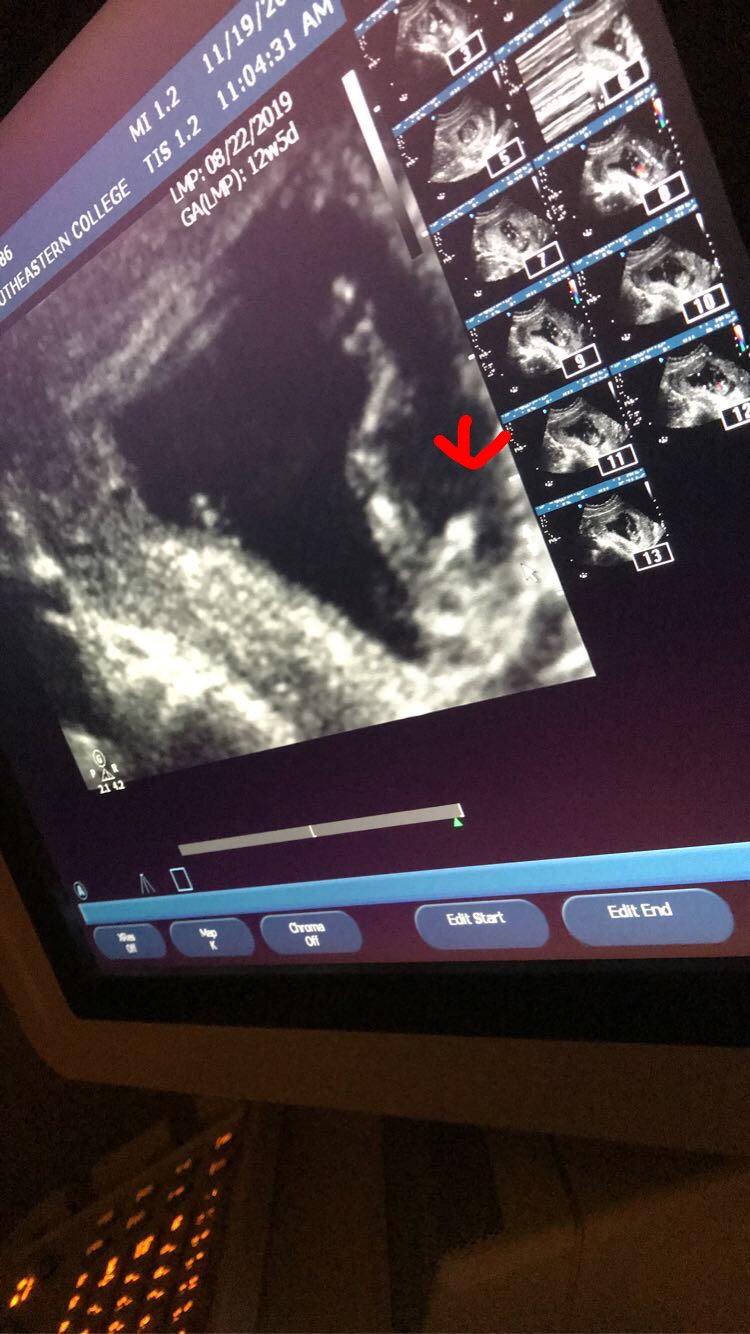

Girl or boy prediction please read thanks.